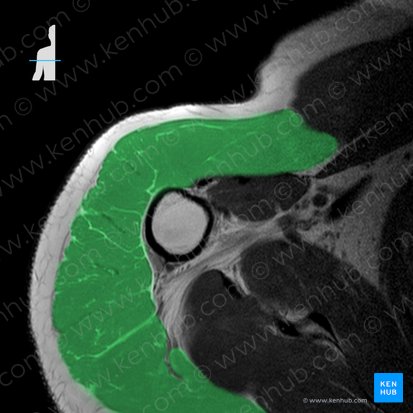

En un corte axial por debajo del acromion podemos ver al músculo supraespinoso, el cual aparece como una estructura grande de forma romboide y de baja intensidad en T1. A medida que continuamos bajando por los cortes podemos seguir al músculo mientras se extiende lateralmente hasta el tendón del supraespinoso, que se ve como una estructura de baja intensidad que rodea la cabeza del húmero hasta insertarse en el tubérculo mayor del húmero. Es importante que analicemos este tendón en busca de cualquier desgarro, ya que entre los tendones del hombro es el que con más frecuencia sufre roturas.

Deltoides

El músculo deltoides tiene un rol sumamente importante como estabilizador del hombro y generalmente es considerado como el músculo principal que actúa sobre la articulación glenohumeral durante la abducción, junto con el músculo supraespinoso. El deltoides puede visualizarse en los cortes por la porción media de la articulación glenohumeral, donde se ve cubriendo el aspecto anterior, lateral y posterior del hombro.

Además, también se puede ver con facilidad al deltoides en las imágenes coronales por el aspecto más posterior, recubriendo la mayor parte del hombro.